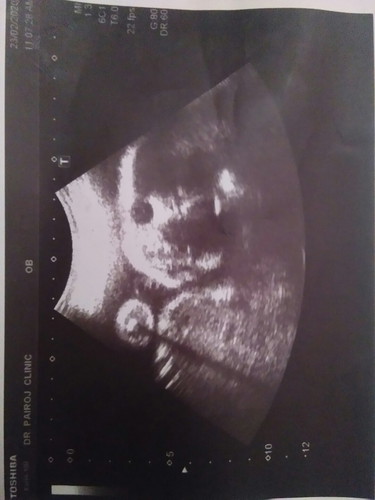

ลักษณะภาพปากแหว่งเพดานโหว่เป็นแบบนี้ไหมคะ

คุณแม่ช่วยดูหน่อยค่ะว่าปากน้องเป็นภาวะปากแหว่งเพดานโหว่ไหมค่ะ ลืมถามคุณหมอคะ

ถ้าซาวด์ช่วงครรภ์น้อยๆ เราจะดูไม่ออกหรอกคะ บางทีเป็นโครงสร้างกระโหลกกับฟัน ถ้าเป็นคุณหมอคงแจ้งทันทีแล้วค่ะ ถ้าดูภาพซาวด์แล้วกังวล ให้ถามคุณหมอทันทีนะคะ

หมอไม่ได้แจ้ง น้องคงไม่ได้เป็นมั่งคะ ภาพถ่ายจากอัลตราซาวด์จะไม่ค่อยชัดอยู่แล้วค่ะ แต่หมอเค้าจะดูออก ถ้าเป็นหมอน่าจะแจ้งนะคะ